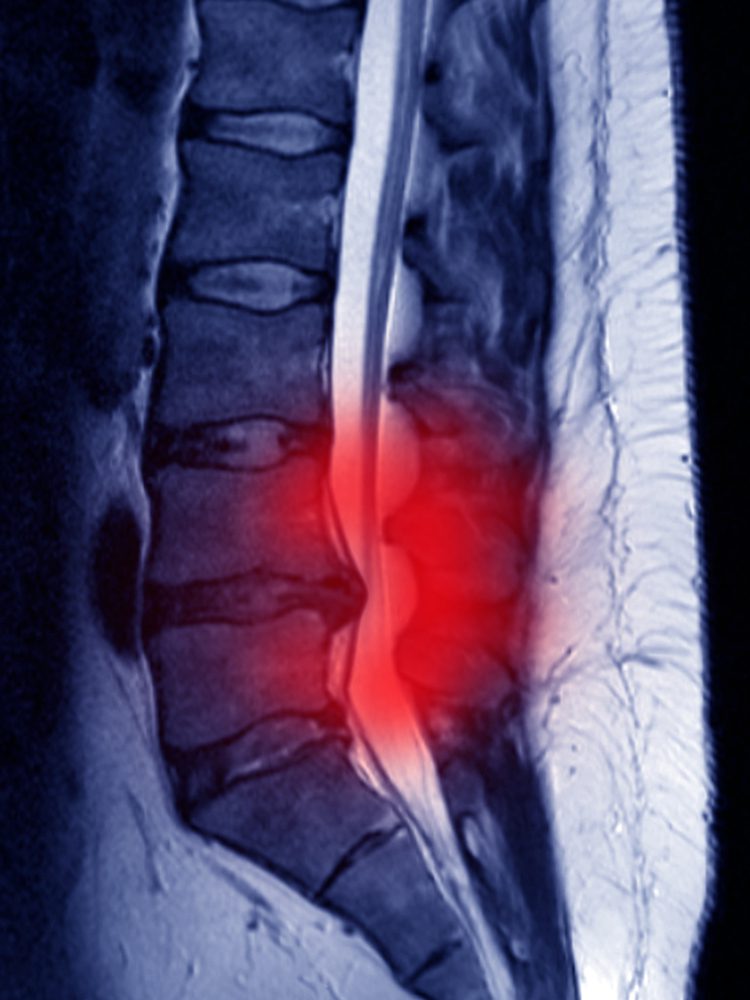

A herniated lumbar disc occurs when the soft, gel-like center of a spinal disc in the lumbar spine (lower back) pushes through a tear in its tougher outer layer. This can compress a nearby nerve root, often causing lower back pain, leg pain (sciatica), tingling, or muscle weakness. Herniated lumbar discs are most common between the ages of 30 and 50, but can affect anyone [1].

When a herniated disc occurs, the gel-like center of the disc (the nucleus pulposus) pushes out through a tear in the tougher outer layer. This can put pressure on the spinal cord and nearby nerve roots, leading to pain, numbness, or muscle weakness. The body’s natural healing process begins immediately after injury. Inflammation develops around the herniated disc, which is the body’s way of starting tissue repair. Over time, the body may gradually reabsorb some of the herniated material, reducing pressure on the nerves and easing symptoms.